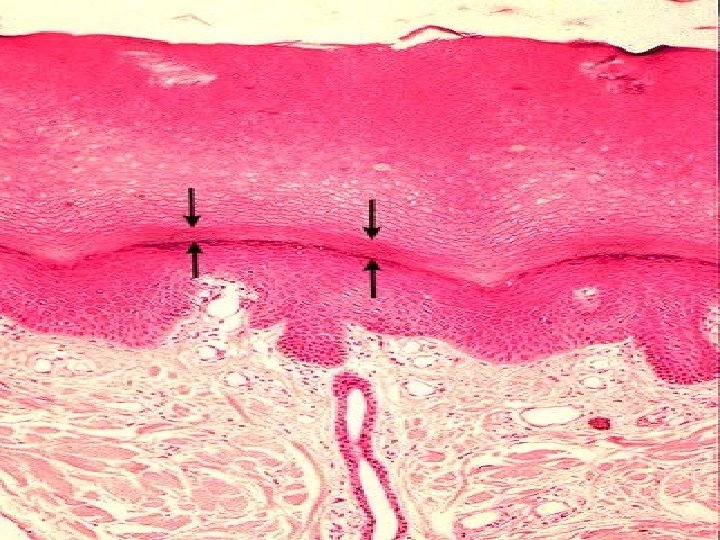

TYPES OF SKIN • Thin skin – covers all parts of the body except for the palms and palmar surfaces of the digits and toes. – lacks epidermal ridges – has a sparser distribution of sensory receptors than thick skin. • Thick skin (0. 6 to 4. 5 mm) – covers the palms, palmar surfaces of the digits, and soles – features a stratum lucidum and thick epidermal ridges – lacks hair follicles, arrector pili muscles, and sebaceous glands, and has more sweat glands than thin skin.

Specific Layers of the Epidermis Stratum Basale: • Mitotic layer, continuously replaces epidermal cells, turnover rate between 25 to 50 days Stratum Spinosum: • Cells are pushed upward and flatten out Stratum Granulosum: • Cells contain granules of Keratin

Specific Layer of the Epidermis Stratum Lucidum: • Observed only in nonhairy or thick skin. Several layers of dead cells with indistinct boundaries Stratum Corneum: • Composed of 25 or more layers of dead squamous cells still joined by desmosomes. Eventually desmosomes break and cells flake off in a process called desquamation